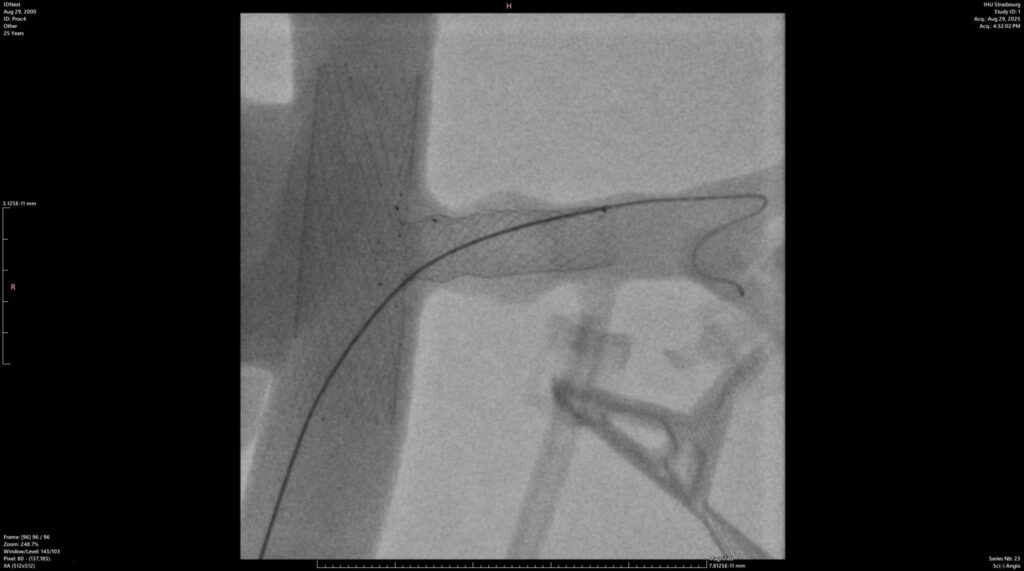

L’accès aux salles hybrides de pointe de l’IHU nous a permis de réaliser une série de tests en conditions quasi-réelles. Au total, 4 procédures d’implantation de nos T-Stents ont été effectuées à l’intérieur d’un modèle in-vitro dédié, le tout sous contrôle radiologique (rayons X).

L’objectif était clair : valider la visibilité du dispositif à l’image et confirmer sa maniabilité pour le chirurgien.

Les résultats ont parfaitement répondu à nos attentes. Les tests ont confirmé une excellente visibilité des produits sous rayons X (voir image ci-dessus) ainsi qu’une grande dextérité d’utilisation pour les opérateurs.